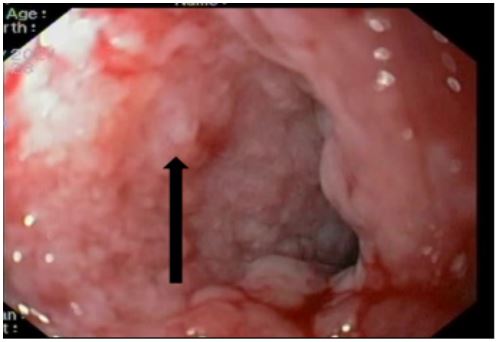

A 59-year-old man has complained of pus and mucus discharge from the anal region, as well as intermittent fever episodes, for the past two years. Three years ago, he developed symptoms of per rectal bleeding and was diagnosed with Carcinoma rectum, for which he received three cycles of neoadjuvant radiotherapy followed by laparoscopic anterior resection with a defuncting descending colostomy. He was discharged on post-operative day 8, with no issues reported. Adjuvant Chemotherapy was administered in 13 cycles. After 6 months of surgery, a CT abdomen was performed, which showed post-op changes in the pelvis with Pelvic peritoneal fat stranding and widening of the presacral space. He was having repeated episodes of fever with chills and pus discharge per anus that were resolved with IV antibiotics. After 6 months, an MRI of the pelvis revealed a significant collection of size 9.1 x 5.2 x 8.8 cm with air loculi at the presacral area-most likely a controlled leak (Figure 2). The conservative approach was continued for another six weeks, during which an intermittent fever with mucus and pus discharge from the anal region persisted. A colonoscopy was performed, which showed the cavity and confirmed the findings (Figure 4). Endovac sponges were sutured to RT and placed directly into the cavity with the help of a colonoscope after debriding and irrigating the cavity. After applying post-E-VAC therapy, the patient improved and had no fever after 48 hours. The procedure was repeated on an OPD basis four more times, with the endovac in place for five days each. At each session of endoscopy, there was a reduction in the size of the sponge used and considerable improvement in terms of the size of the cavity and the amount of slough (Figure 5). The cavity completely healed 10 weeks after E-VAC therapy, and the patient has been asymptomatic for the past 4 months. A CT scan showed complete resolution of the leak.

Figure 5: Healing of rectal cavity after E- Vac.

In the first case, postoperative anastamotic leak in the anocolic region is a severe condition that negatively impacts postoperative outcomes. In conventional practise, in cases where a patient exhibits a symptomatic leak, the anastomosis is typically defunct, either as an initial procedure or subsequently. If abscesses are present, they are commonly drained either through percutaneous or transanal methods. Under the application of standard conventional management practises, it is possible that approximately 50% of these leaks may be resolved [6]. However, the development of a chronic presacral sinus occurs in the event that these leaks persist. The treatment for this chronic sinus condition necessitates a significant surgical intervention involving the removal of the leaking anastomosis. Subsequently, either a new anastomosis or an inter-sphincteric proctectomy with omentoplasty and the establishment of a permanent colostomy are performed [7]. Preventing the progression of a leak into a chronic sinus condition is of utmost importance, as it necessitates significant surgical intervention. In this particular case, a treatment approach utilising Vacuum-Assisted Drainage (EVAC) was employed, which involved the gradual reduction of Endosponges to facilitate the desired collapse of the cavity. The application of endovac therapy demonstrated a success rate of 90% in a cohort of 20 patients who experienced a rectal anastomotic leak. Notably, the leaks observed were extra-peritoneal in nature, and no diversion was employed for sepsis control. The therapy exhibited positive outcomes in terms of promoting granulation of the leak cavity and ensuring survival without the need for a stoma. Two patients required balloon dilatation for luminal stenosis [8].